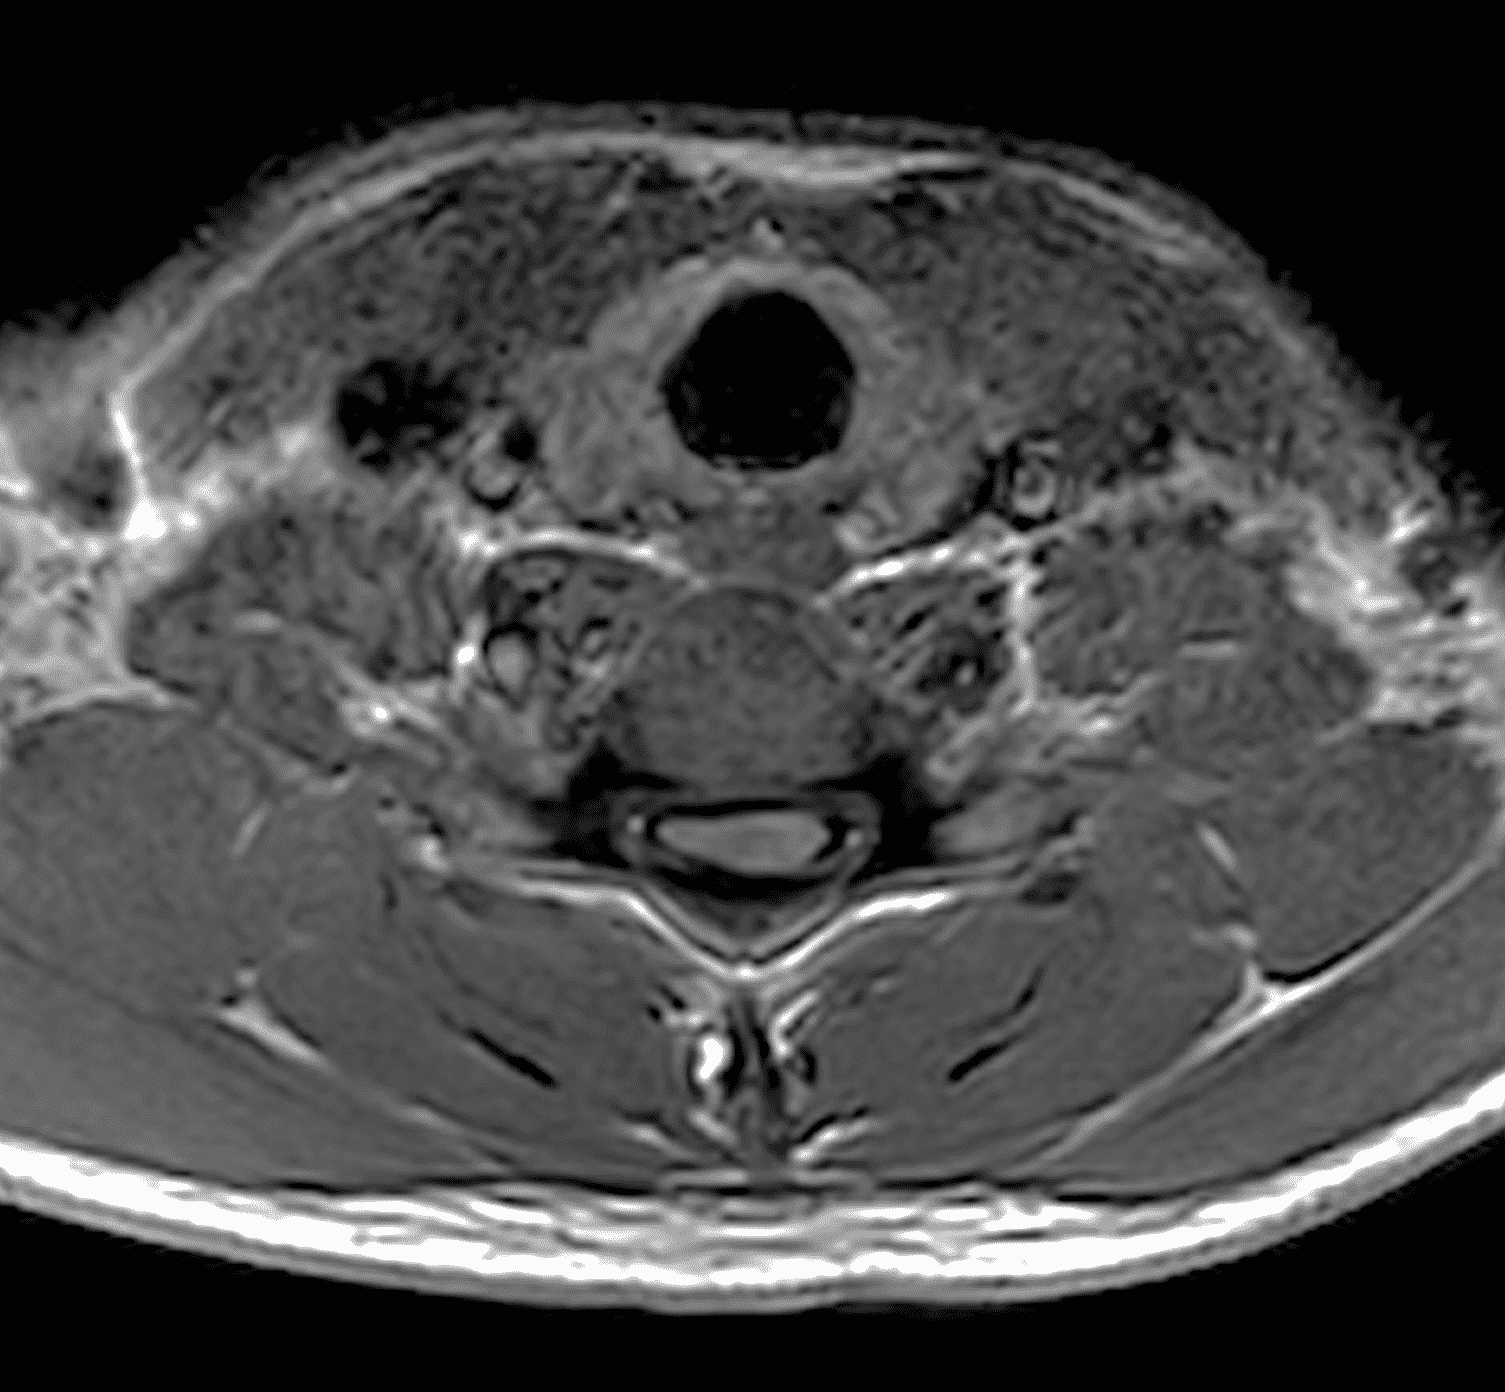

Figure 2: Neutral images of the cervical spine. Sagittal (2A) T2-weighted, (2B) T1-weighted, and (2C) STIR images show mild kyphosis, an enlarged posterior epidural space with loss of attachment of the dura (red arrows), and cord atrophy at the C6 level (yellow arrow). Subtle cord hyperintensity on the water sensitive images at the C7 level (green arrows) likely represents gliosis. (2D) Axial T2-weighted image shows enlargement of the posterior epidural space, right greater than left (red arrows). (2E) Axial T1-weighted image shows an enlarged posterior epidural space (red arrows) and cord atrophy, more severe on the right (yellow arrow).

Chen et al.29 investigated the sensitivity and specificity of these previously suggested neutral position MRI findings and a new proposed finding of loss of attachment (LOA) of the posterior dura from the subjacent lamina. The localized lower cord atrophy and asymmetric cord flattening can be appreciated on axial and sagittal MRI and is most commonly seen at the C4 to C7 levels. This finding is best assessed on axial images since sagittal images may result in erroneous assessment if the cord is not truly at midline. Additionally, comparing axial images to the normal level below is most reliable as the normal cord starts to enlarge at C3, reaches maximum dimension at C5, and tapers below T1. Localized cord atrophy had a sensitivity of 58.7% but specificity of 100% for HD and was not seen in the normal control group.

Asymmetric cord flattening is best assessed on axial T2-weighted images and is defined as cord flattening without narrowed or obliterated adjacent subarachnoid space to avoid confusion with compression due to adjacent spurs or herniated disc. An elliptical spinal cord is considered normal. A pear-shaped cord is seen with asymmetric cord flattening, and a triangular shaped spinal cord is considered symmetric cord flattening. Asymmetric cord flattening was found to have a sensitivity of 69.6% and specificity of 100% for HD.